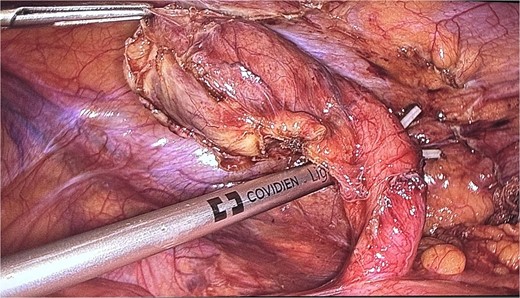

The patient was admitted and scheduled for a laparoscopic appendectomy. During surgery, the appendix was identified in the retrocecal position, extending to the right paracolic gutter. It was dissected from surrounding tissues, revealing a large mass at the tip and multiple nodules on its surface. The surgical team employed minimal manipulation techniques to avoid tumor rupture, suspecting a carcinoid or other appendicular tumor (Fig. 4). The mesoappendix was dissected and transected at the base using an EndoGI stapler. The specimen was removed in a bag and sent for histopathology (Fig. 5).

An intraoperative picture of an acutely inflamed appendix with mass seen at the tip; the mass was manipulated carefully and grasped at peri-appendicular tissue to avoid mass rupture.

Due to diagnostic uncertainty at initial presentation, surgeons must use careful and minimal manipulation techniques to avoid tumor rupture. In this case, the appendicular mass mimicked a carcinoid tumor intraoperatively, so minimal manipulation techniques were employed by grasping the appendix with periappendicular tissue. The mesoappendix was dissected at its root to obtain as many lymph nodes as possible to assist the pathologist in making a final diagnosis, especially in cases of malignancy. Clinicians should always consider various differential diagnoses of acute appendicitis, including AD, when evaluating patients with right lower quadrant abdominal pain [3].